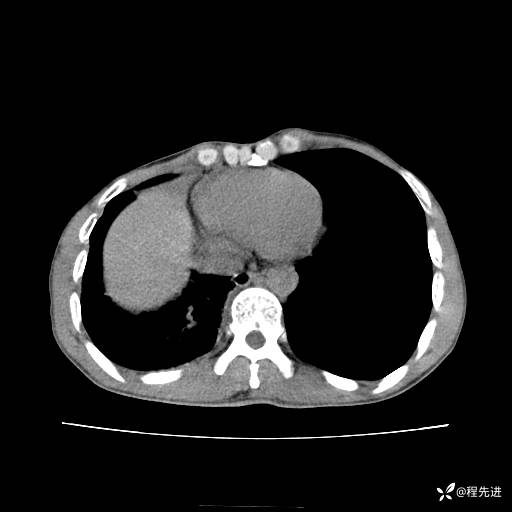

患者性别:男

患者年龄:49岁

主诉:咳嗽、胸痛1周

简要病史:1周前受凉感冒后开始出现咳嗽症状,阵发性连声咳,痰多,黄白痰,不易咳出,伴胸痛、气紧、胸闷,右侧为主,活动用力、呼吸时胸痛明显,曾在当地诊所贴敷膏药仍疼痛

体格检查:T:36.3 ℃ P:80 次/分 R:20 次/分 BP:120/88 mmHg,指脉氧饱和度97%,意识清晰,呼吸平稳,右侧第二、三肋骨压痛,可见膏药贴敷,皮肤无异常,双肺呼吸音粗,未闻及干湿性啰音。心率80次/分,节律整齐,无杂音。腹平软,全腹无压痛无反跳痛

临床诊断:社区获得性肺炎

CT平扫: